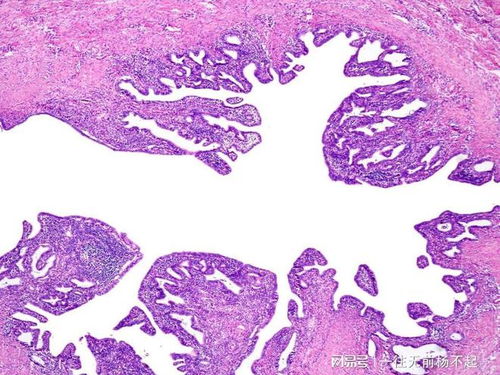

的一项研究由英国利物浦大学的Anna Maria Geretti教授领衔展开的调查带来了令人沮丧的消息。这一研究揭示了HIV病毒的一种狡猾策略,它在治疗期间会藏匿在能够触发免疫应答的血细胞中,从而避免被彻底清除。研究者发现,HIV通过将其自身的遗传信息嵌入CD4免疫系统中实现这一目的。

研究者们针对一系列接受抗逆转录病毒疗法长达1年至14年的患者进行了详尽的检查,以确认这些患者体内HIV嵌入CD4细胞的状况。结果令人震惊,所有患者的HIV嵌入水平保持了一致性。这表明当HIV感染的CD4细胞自我复制、生成更多细胞时,这些细胞同样复制了艾滋病毒的基因。